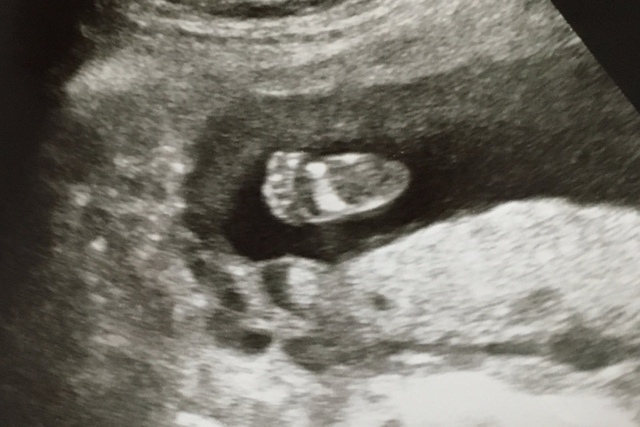

17週4日(17w4d・性別不明)|けのす さん(30歳)

エコー写真撮影時のエピソード:

毎回ちゃんと成長しているのか、ドキドキしながら妊婦健診へ行きます。もしかしたら性別がわかるかもしれないという週数でしたが、残念ながらわからず、でもかわいい小さな足の裏のエコーを先生が上手く撮ってくれて、ほっこりしました。なんども見直してしまいます。